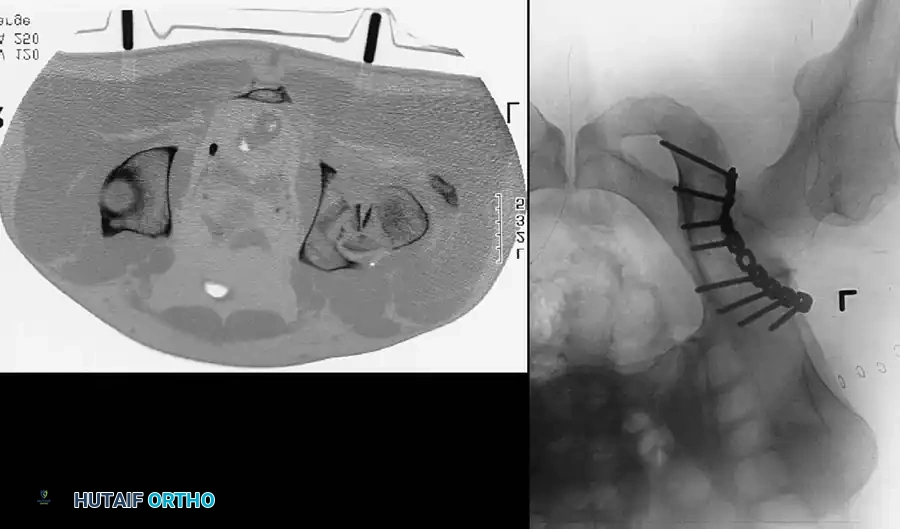

CT scan of the pelvis providing detailed visualization of the posterior wall comminution and the relationship of the femoral head to the acetabular columns.

Preoperative and postoperative radiographs demonstrating a complex fracture-dislocation successfully managed with open reduction and internal fixation.

Postoperative radiograph showing anatomic restoration of the posterior acetabular wall utilizing a contoured reconstruction plate and lag screws.

Axial CT and corresponding radiograph demonstrating precise plate placement along the posterior column to buttress the posterior wall fracture.